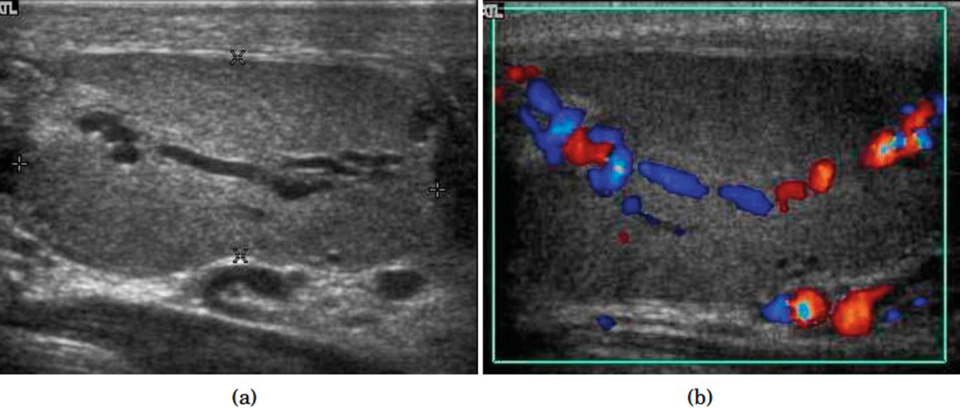

Intratestikuläre Varikozele. Es sind dilatierte röhrenförmige Strukturen zu erkennen (links). Vaskulärer Reflux während des Valsalva-Manövers (rechts). Intratestikuläre Varikozele. Es sind dilatierte röhrenförmige Strukturen zu erkennen (links). Vaskulärer Reflux während des Valsalva-Manövers (rechts). © wikimedia/Chee-Wai Mak and Wen-Sheng Tzeng

Dilatierte röhrenförmige Strukturen zu erkennen (links). Vaskulärer Reflux während des Valsalva-Manövers (rechts). Dilatierte röhrenförmige Strukturen zu erkennen (links). Vaskulärer Reflux während des Valsalva-Manövers (rechts). © wikimedia/Chee-Wai Mak and Wen-Sheng Tzeng